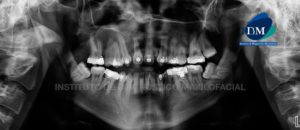

Paciente masculino, 16 años de edad, es referido al Instituto de Diagnóstico Maxilofacial (IDM) para evaluación tomográfica por retraso en la erupción de segundas premolares